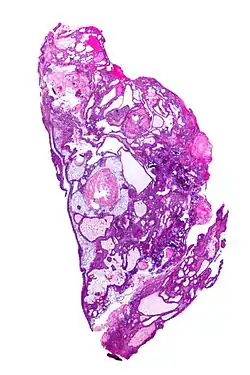

| Very low magnification micrograph of an adamantinomatous craniopharyngioma. HPS stain. | |

Micrograph showing the characteristic features of an adamantinomatous craniopharyngioma - cystic spaces, calcifications, and "wet" keratin, HPS stain -

On macroscopic examination, craniopharyngiomas are cystic or partially cystic with solid areas. On light microscopy, the cysts are seen to be lined by stratified squamous epithelium. Keratin pearls may also be seen. The cysts are usually filled with a yellow, viscous fluid rich in cholesterol crystals. Of a long list of possible symptoms, the most common presentations include headaches, growth failure, and bitemporal hemianopsia.